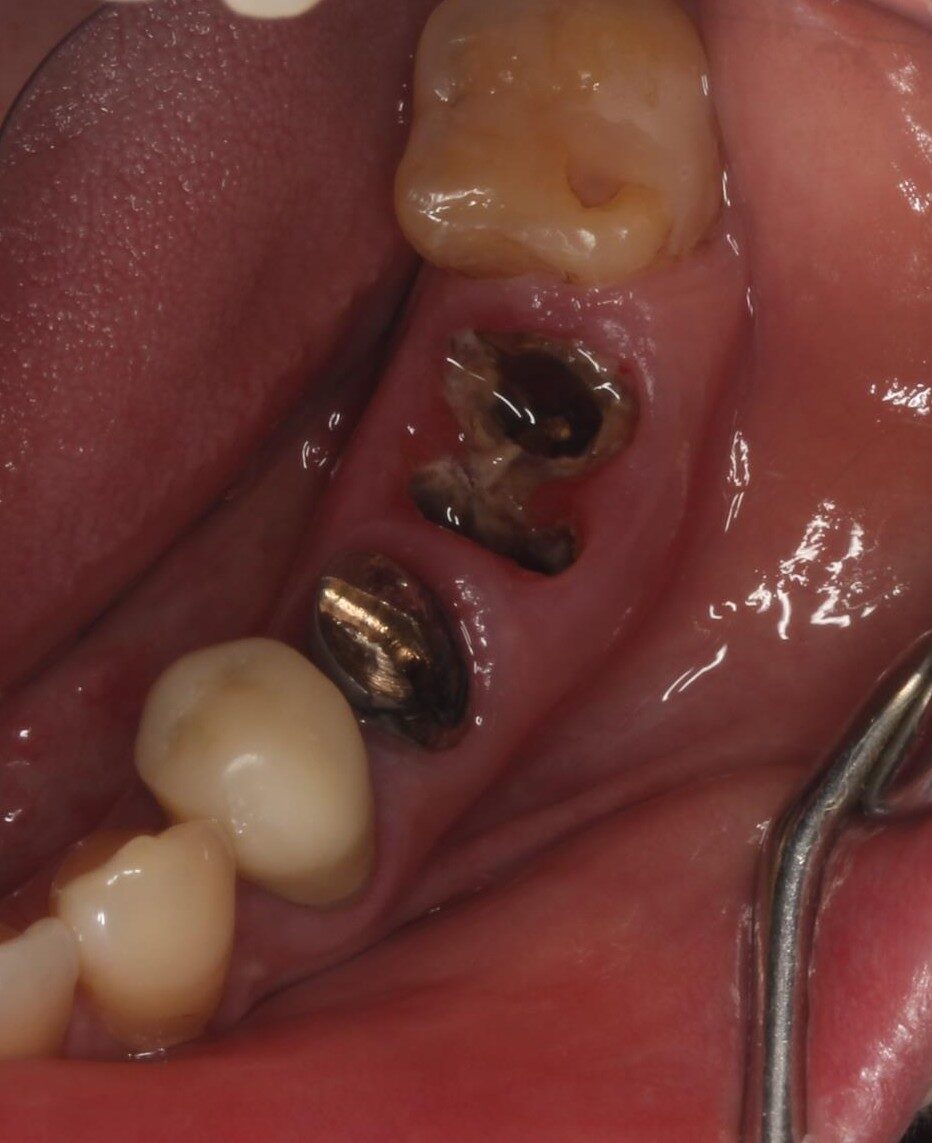

症例02

70代 男性 咬み合わせが強く多くの歯がすぐに壊れる

| 主訴 | 咬み合わせが強く、治療をしてもつくった歯がすぐに壊れる。 他院ではインプラントをいれることも難しいため、断られた。 |

| 年代・性別 | 70代 男性 |

| 治療部位 | 下顎両側 5,6 上顎右側 4 6のインプラントブリッジ ※全顎的に、臨床的歯冠長延長術(クラウンレングスニング)を行い、セラミッククラウンの強度を増しています。 |

| 治療費用 | インプラント 440,000円×6本 |

| 手術回数 | 下顎1回 上顎1回 |

| 治療期間 | 下顎6ヶ月 上顎6ヶ月 |

| 手術時間 | 下顎90分 上顎60分 |

| 治療回数 | 下顎1回 上顎1回 |